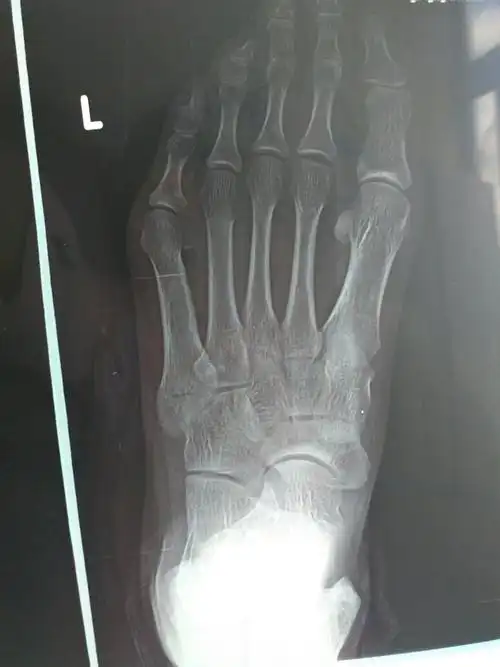

大夫你好,我脚外侧崴了25天了还是不敢走道,一用力就疼,崴脚第二天拍